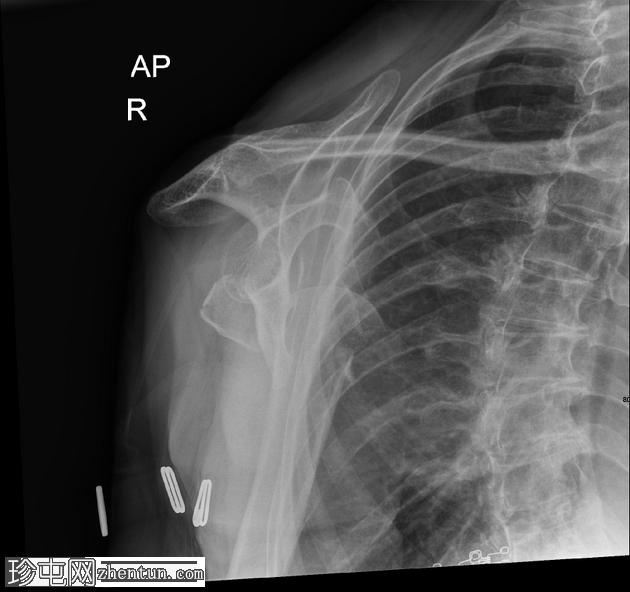

2.png

斜位

右肱骨近端粉碎性骨折,严重移位,累及肱骨颈和肱骨大结节,伴肱骨近端相对于肩胛盂的前下脱位和肩关节脂肪血肿。肩锁关节完整;另可见胸椎侧弯、右侧颈部手术夹以及覆盖上臂和腋窝的衣物痕迹。

该X线片显示右肩高能量损伤,表现为肱骨近端粉碎性骨折,严重移位,累及肱骨颈和肱骨大结节。伴随的前下肩关节脱位反映了稳定软组织结构的破坏,这是此类骨折脱位模式的常见特征。脂肪血肿的存在表明骨折已延伸至关节内,骨髓脂肪渗入关节腔;这是评估损伤严重程度的重要影像学线索。